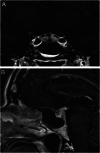

Results: Nine hundred and fifty-four patients received ICI therapy during the study period, and 37 (a prevalence of 3.9%) developed hypothalamic-pituitary-adrenal axis dysfunction. Their mean age was 65 years, and 70% were male. About 86.5% of the total patients affected were treated for metastatic malignancies. Ten of the 37 patients died during follow-up as a direct consequence or complication of their primary cancer diagnosis. The median interval for the onset of symptoms was 4 months. Following repeated testing, there was no recovery in cortisol or ACTH levels for any individual. Other permanent anterior pituitary hormone defects were unusual. Hypophysitis associated with immunotherapy appears to specifically target the corticotrophs, with no evidence of recovery over time. There was a specific abnormality seen in MRI scans of 7 of 27 patients who had scans, which appeared to be a particular feature of immune-mediated hypophysitis. These were confined to the anterior aspect of the pituitary gland, appearing as striations, and were not visible on any of the scans performed more than 3 months after the likely onset of the disease.

Conclusion: These data show that immune-related hypophysitis is a common complication of immune checkpoint inhibitor therapy. This may result in an imaging abnormality within the areas of the pituitary that are richest in corticotrophs. The endocrine consequence of this is a permanent defect in ACTH and, therefore, cortisol production.